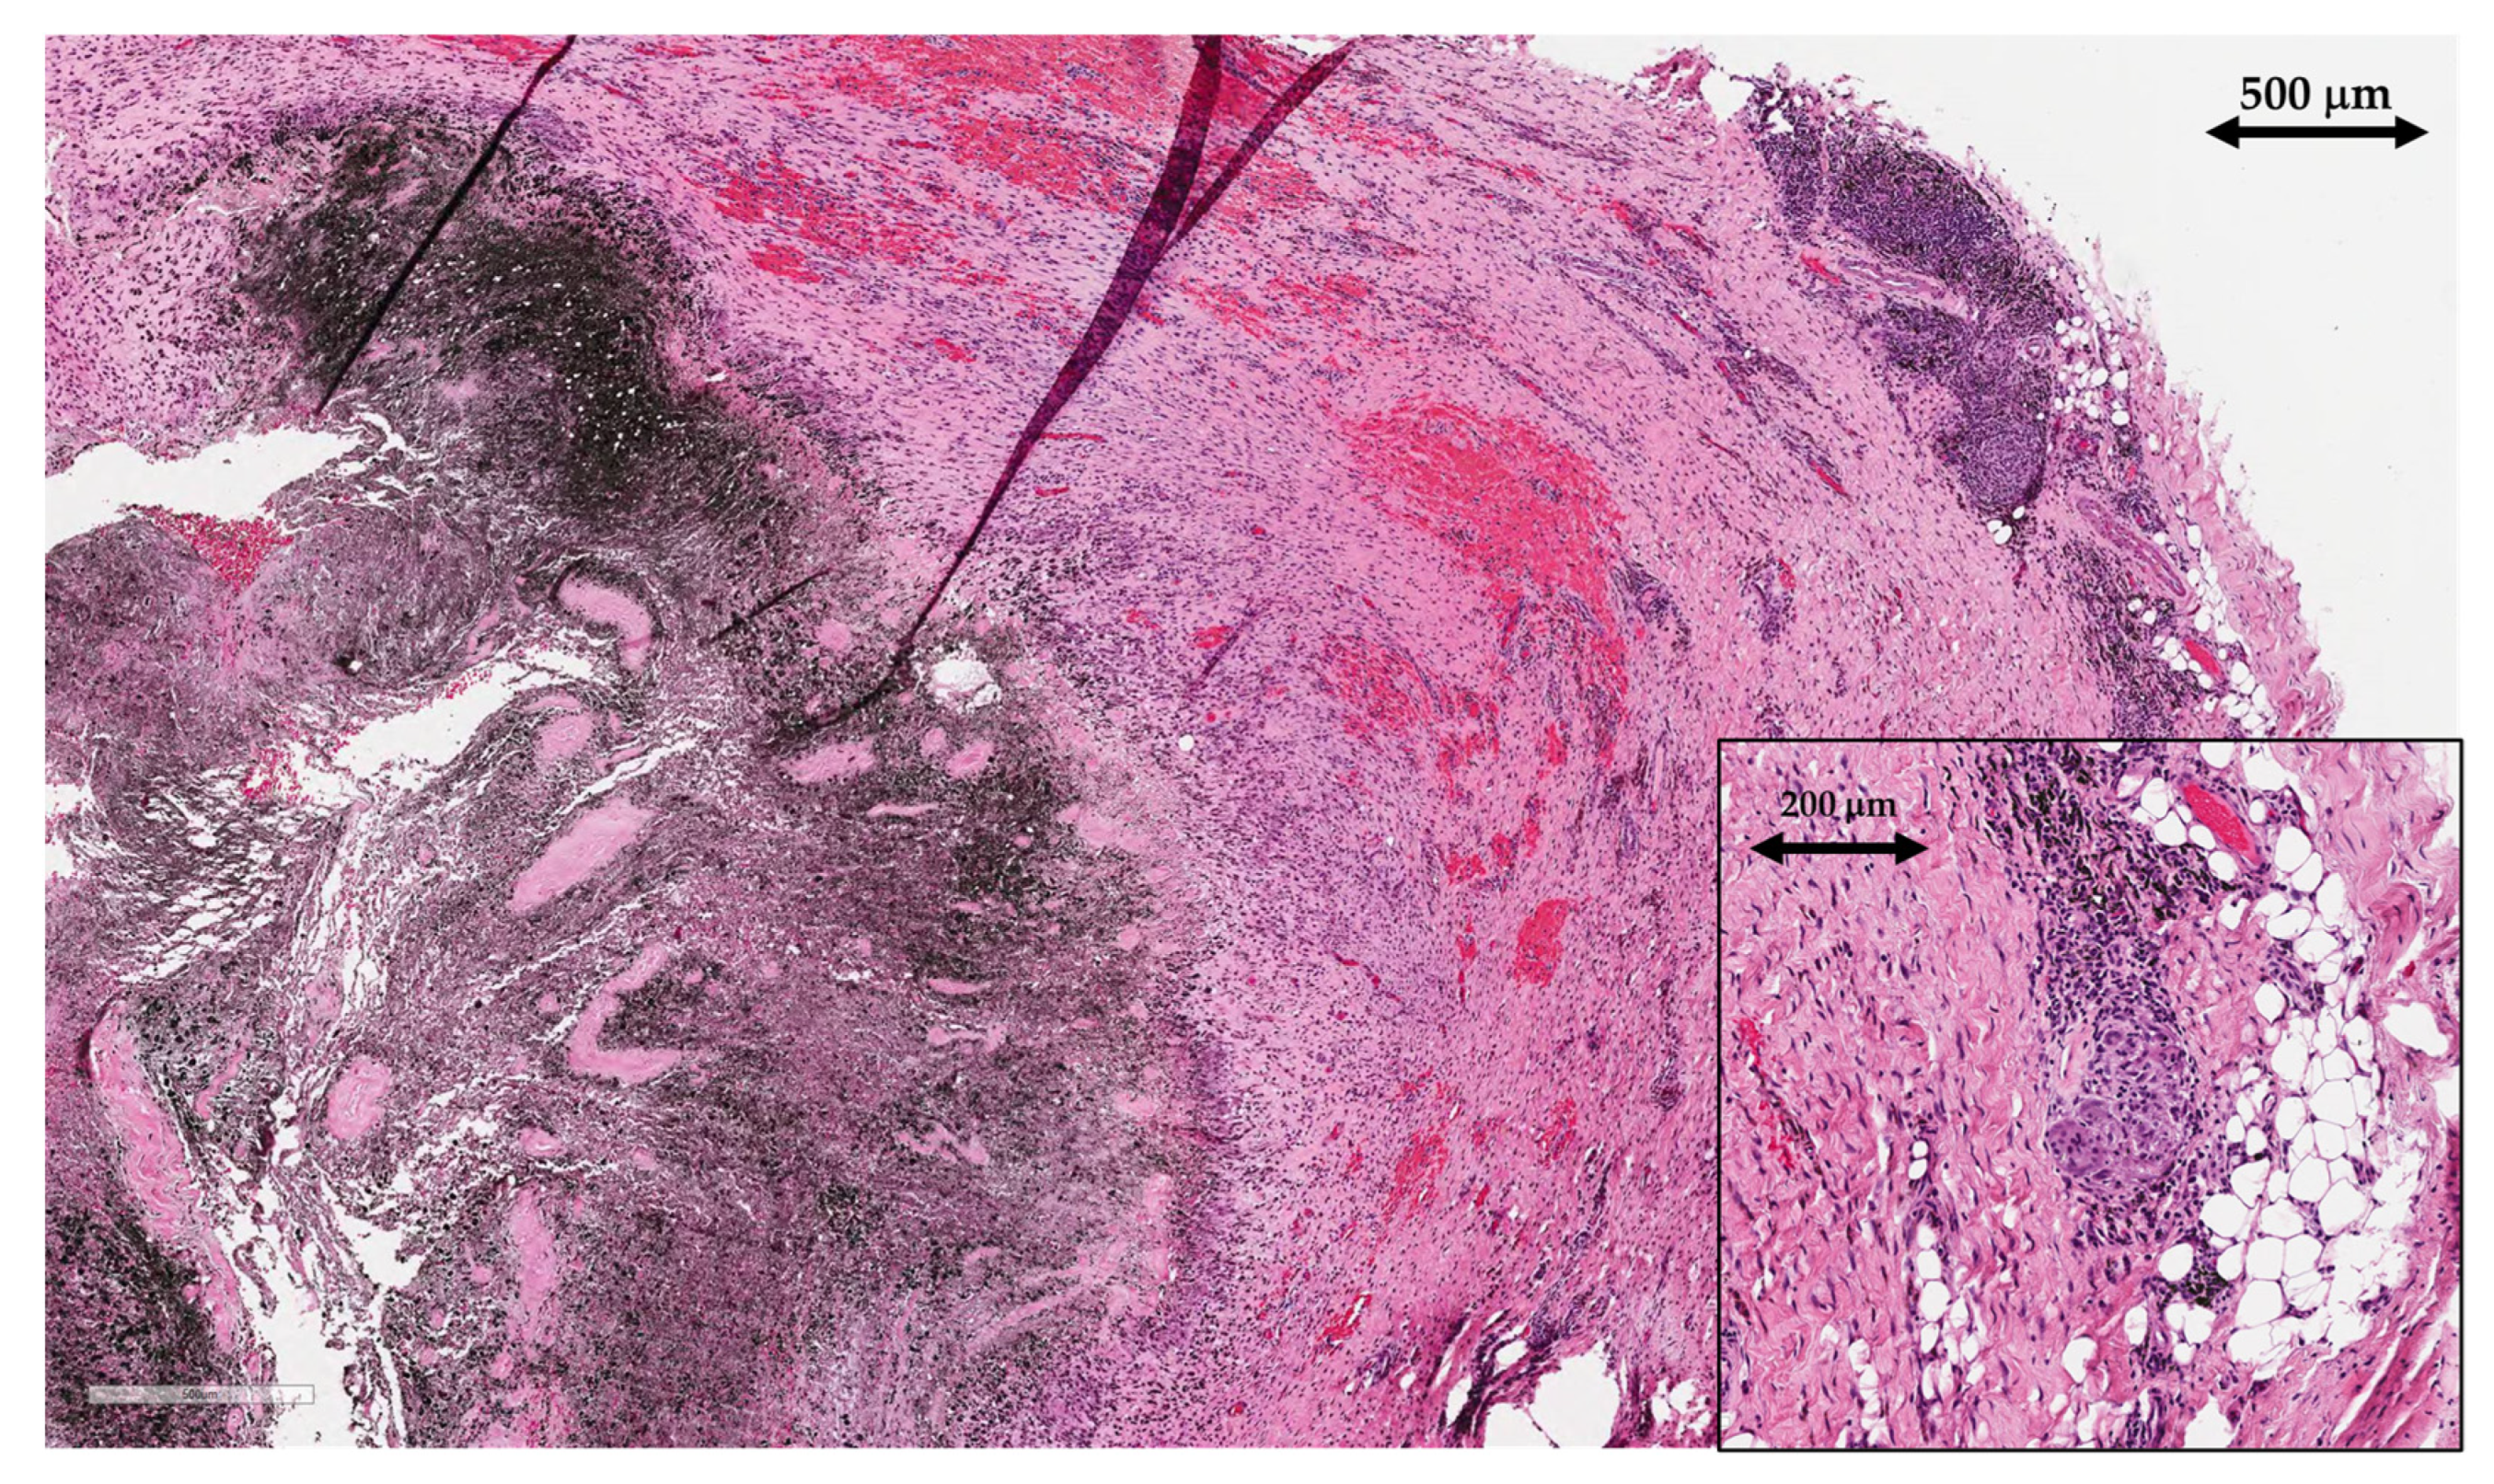

2.2. Histological Analysis